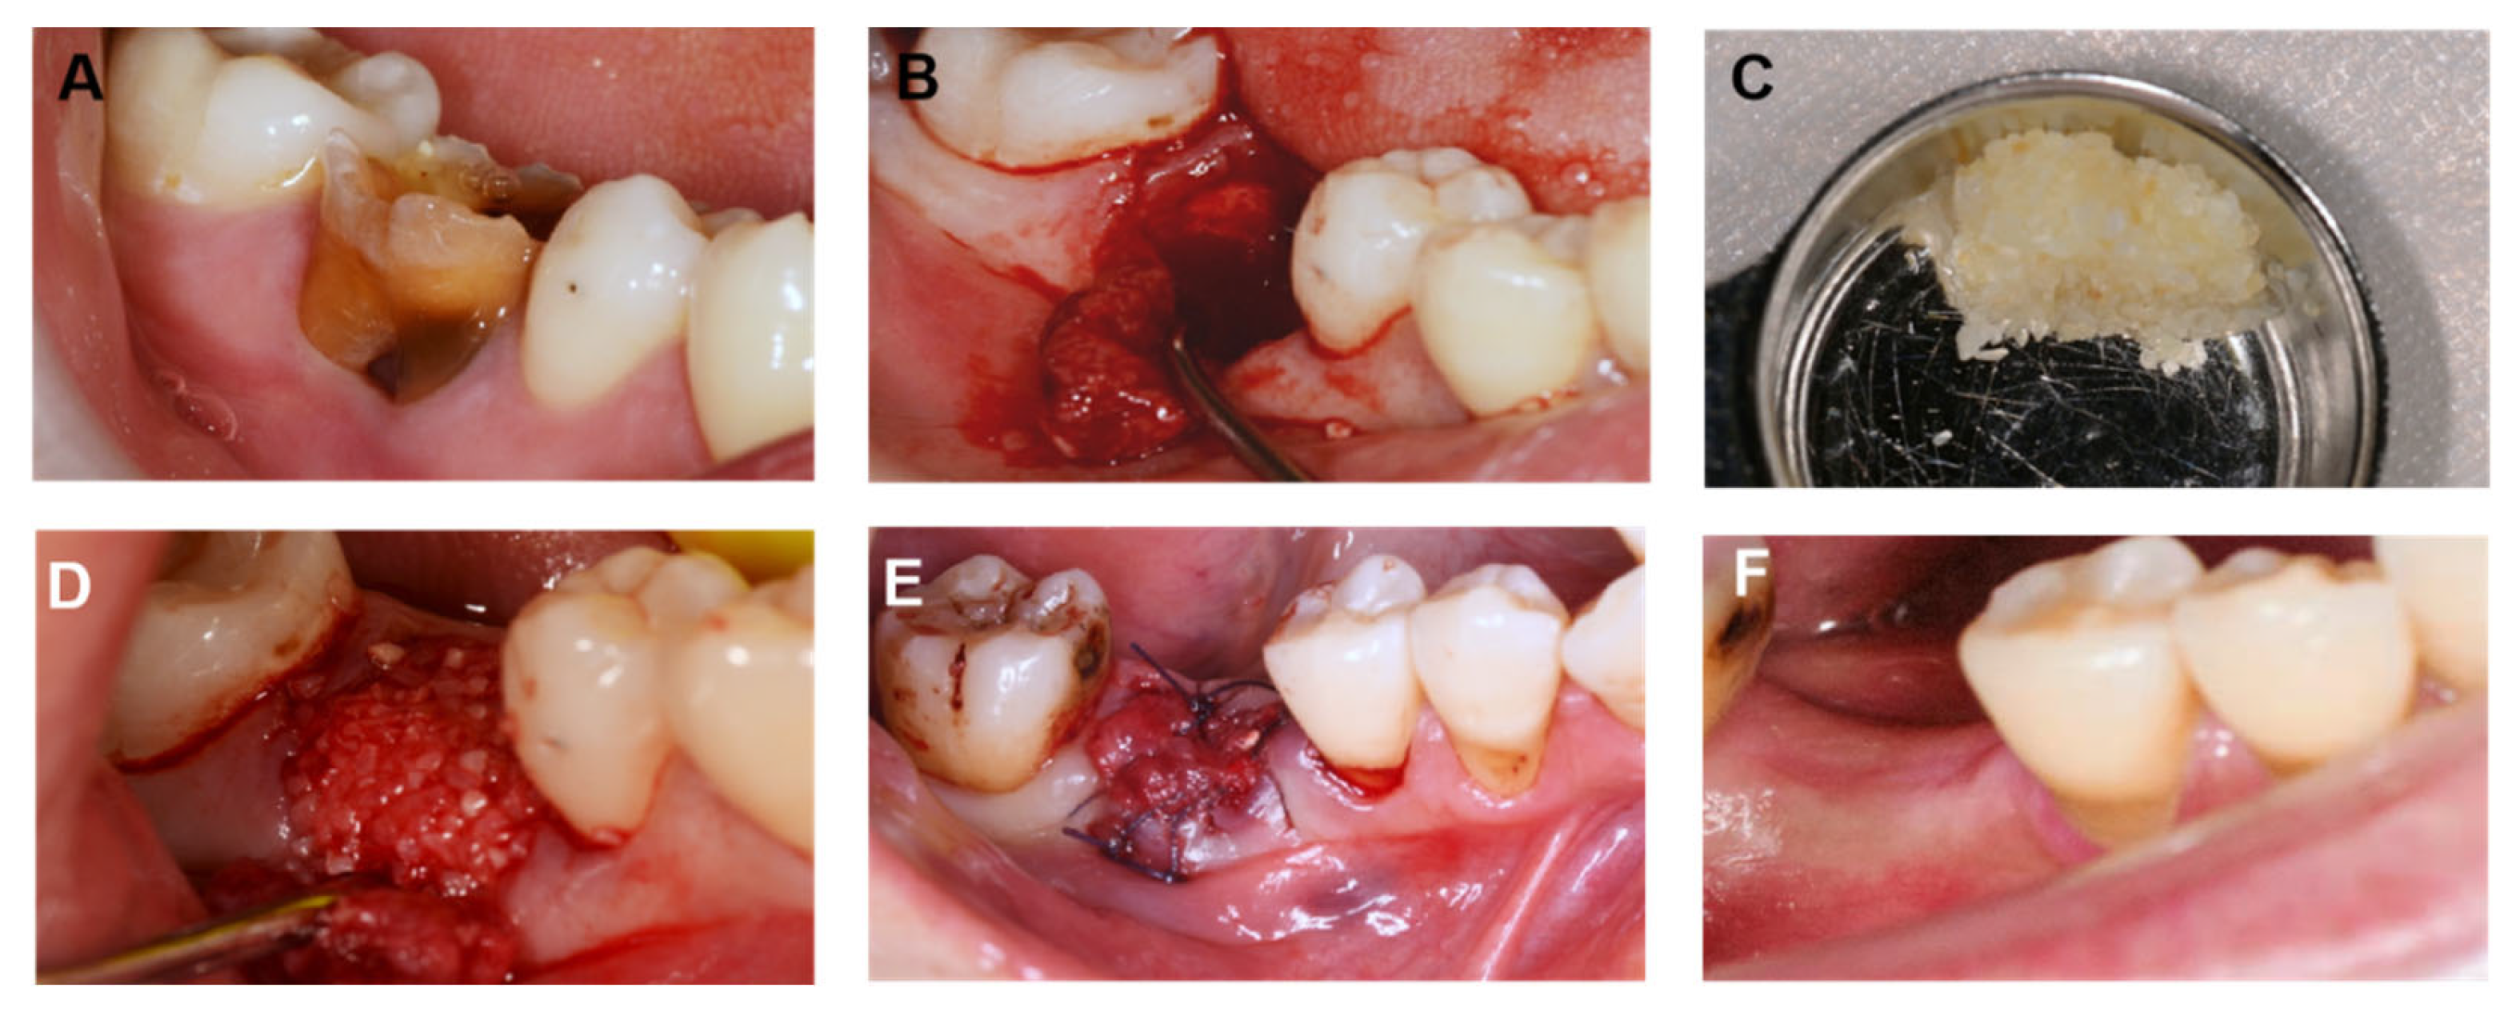

2.4. Surgical Method

4. Case Report